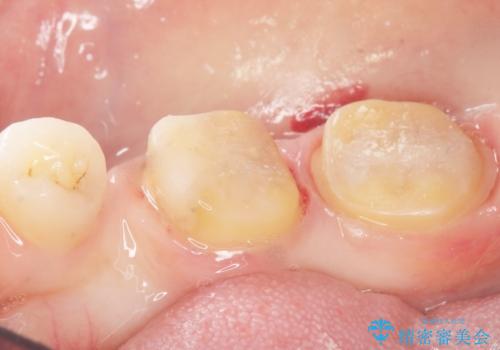

- 奥歯の隙間を治したいとご希望された患者様です。

学生時代に舌側矯正されていたものの、通院が大変になり治療を途中でやめてしまい、奥歯の間に隙間が残ってしまったそうです。

矯正せずに早く治したいという強いご希望とう蝕があることから、セラミッククラウンによる補綴治療で隙間を閉じることにしました。